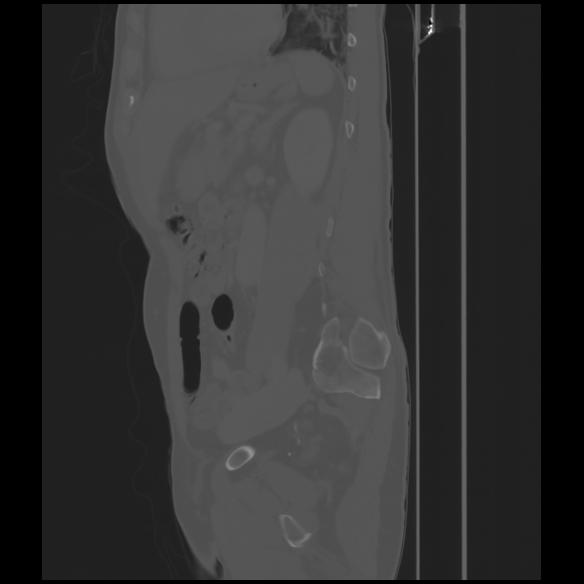

7 CUERPO,CE,Sagittal,3.000,CUERPO,Sagittal,